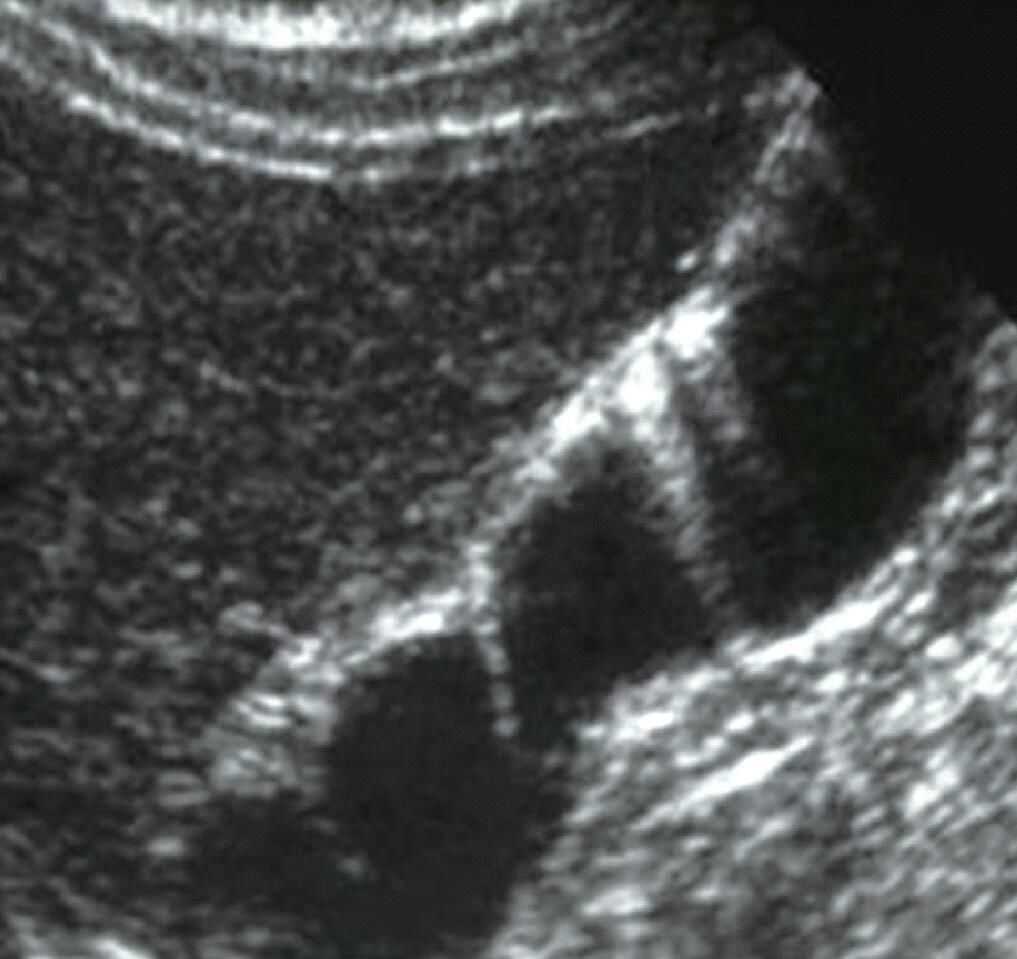

(4)部分容积效应:超声波形状特殊而且波束较宽,由超声断层扫描时断层较厚引起,例如:肝脏的小囊肿内可能表现为低回声(来自小囊肿旁的部分肝实质),或膀胱后壁因部分容积效应显示不清晰(图9)。

图9膀胱后壁因部分容积效应边缘显示不清晰